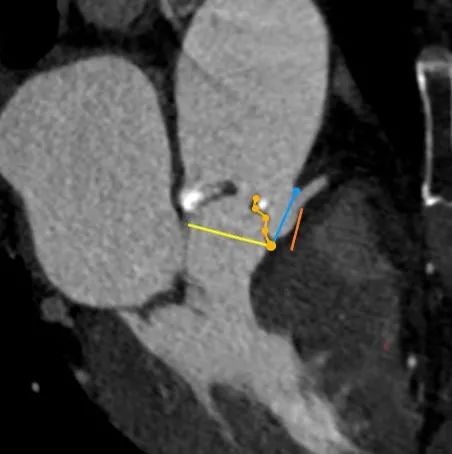

RCA

下缘高度 10.2mm

上缘高度 11.9mm

瓣叶长度 12.7mm

LCA

下缘高度 7.1mm

瓣叶长度 11.8mm

● 冠脉开口高度低,结合窦部高度和宽度、STJ大小、瓣叶长度等,冠脉闭塞风险高,根据预扩张结果决定是否行冠脉保护。